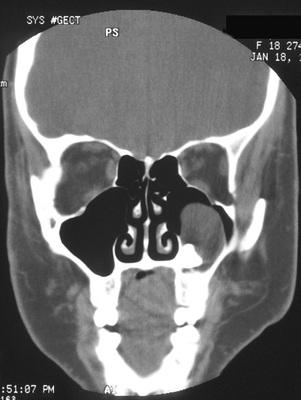

Computed tomography (CT) scan showing a large cyst involving the crown of an unerupted maxillary third molar.

odontogenic keratocyst (OKC)